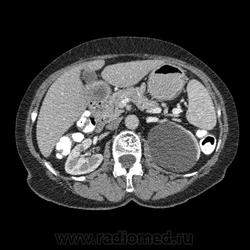

Впечатление, что дуля эта вне головки п.ж., интрамурально в луковице, что ли... тогда возможно GIST, но надо дайком. Утолщение подслизистой в антральном отделе желудка, не удается проследить переход от желудка к 12-перстной((. Внутрипросветно/внутристеночно - не разобрать. 1 фаза?

Клинику! Есть ли признаки высокой тонкокишечной непроходимости, что при ФЭГДС в 12-перстной - туда удалось пройти или нет? ААА! Одни вопросы))))

В-общем, варианты такие без дайкомов: пролапс слизистой в 12перстную, безоар, внутрипросветный дивертикул, гастроинтерстинальная опухоль. И большие сомнения, что это в головке п.ж. - оно отделено от неё тонким слоем жировой клетчатки

Фаз было 3. Видео не выставлял прошлый раз пришел ответ из сайта что видео не работает на сайте Идет накопление контраста в нативе в центре +2+4 по периферии +32+34 .в артериальную +20 и +65 +70 соответственно.

Что оно копит - бог с ним... если это пролапс слизистой, то суммация стенок. Безоар бы не копил. Напрягает отек слизистой в антрале... Это должно быть скорее внутри просвета кишки, т.к. оттесняет газ в 12-перстной на периферию. Без дайкомов больше ничем не могу, извините. Подождём мнения коллег.

Как мне видится - пролапс слизистой желудка в 12-перстную. А мнения коллег что-то нетути...

А что растет из левой почки? Может оно же и желудок сдавливает?

Это расширение всей 12- перстной кишки (стаз).